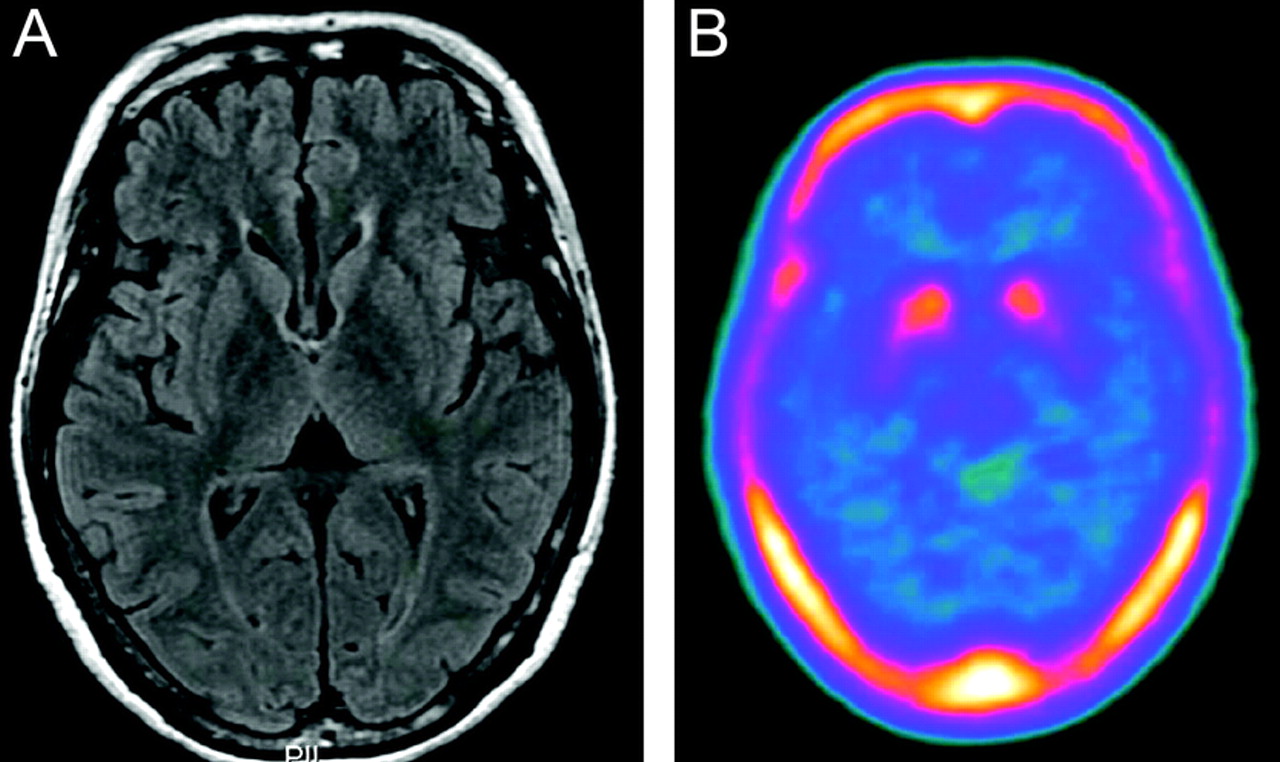

我们确定了一个小说常见的错义替换,2236 g > A (Ala746Thr)外显子20日在一个杂合的状态在两个指数病人来自台湾;一个是患者零星EOPD (Y56)被发现携带一个杂合的PINK1突变(M341I)12和另一个晚发性家族性PD (F37) (图1一个)。这部小说变体随后确认了在另一个病人的零星EOPD 111指数从新加坡患者在第二部分的研究中,但没有观察到1178年总从589等位基因控制。188金宝慱官网下载变异的频率在EOPD和家族性帕金森病是1.7%(3 182名患者的EOPD有/没有家族病史)。变体没有观察到589年种族匹配控制样本。这种变异的频率明显高于PD情况下比控制(p= 0.01,相对危险度4.3,95%可信区间1.9 - -4.3)。索引的父亲病人F37显然是被诊断为帕金森病但cosegregation分析DNA样本在这个家庭并不可用。病人的临床表型ATP13A2Ala746Thr类似于特发性帕金森病(表上e 1首页®网站www.首页neurology.org)。头先生的形象F37是正常没有皮质萎缩和的证据18F-6-fluorodopa (18F-dopa) PET扫描显示下降18F-dopa吸收正确的内果皮,兼容左hemiparkinsonism (图2)。宠物发现类似模式中观察到典型的特发性帕金森病。

图2头MRI和18F-dopa PET扫描以防F37 ATP13A2突变

(一)头部MRI显示没有明显的皮质萎缩。(B)18F-dopa PET扫描显示双边下降18F-dopa吸收,特别是左壳,这是兼容的临床症状。

而成熟的神经退化的原始Kufor-Rakeb综合症有症状的家庭,4我们的杂合的患者Ala746Thr变异表现出温和的典型临床表现与PD,包括18F-dopa宠物的发现。然而,证明Ala746Thr致病性的一个杂合的状态并不容易。鉴于这种替代的结果没有被观察到在1178年种族匹配控制染色体,我们建议Ala746Thr可能不是一个常见的多态性。此外,这种变异的频率明显高于PD情况下比控制(p= 0.01),这意味着这种罕见的变异的ATP13A2与PD在亚洲人口的风险增加。